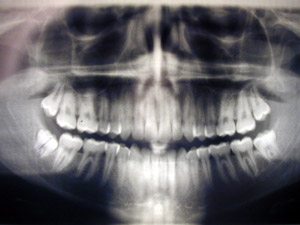

It’s five days since I had four wisdom teeth removed and the stitches are itching. When I told people I was having this done the response was amazing, each person had their own story to tell, most of them could have featured in a top Halloween movie line up. This did not put me at ease.